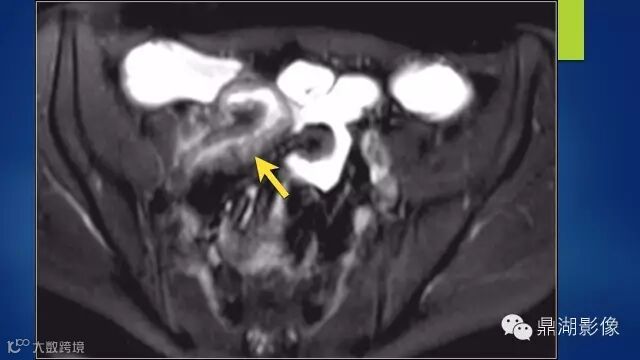

what's the meaning of fat halo sign?

粘膜下水肿或脂肪沉积,可致肠壁内呈低密度层(halo征),其最初用来描述溃疡性结肠炎,是良性肠道病变的结果,无特异性,也可存在于放射性肠炎,移植-受体疾病和慢性缺血性肠炎以及单性的肥胖症患者。

Fat halo aslo can be seen in normal terminal ileum.